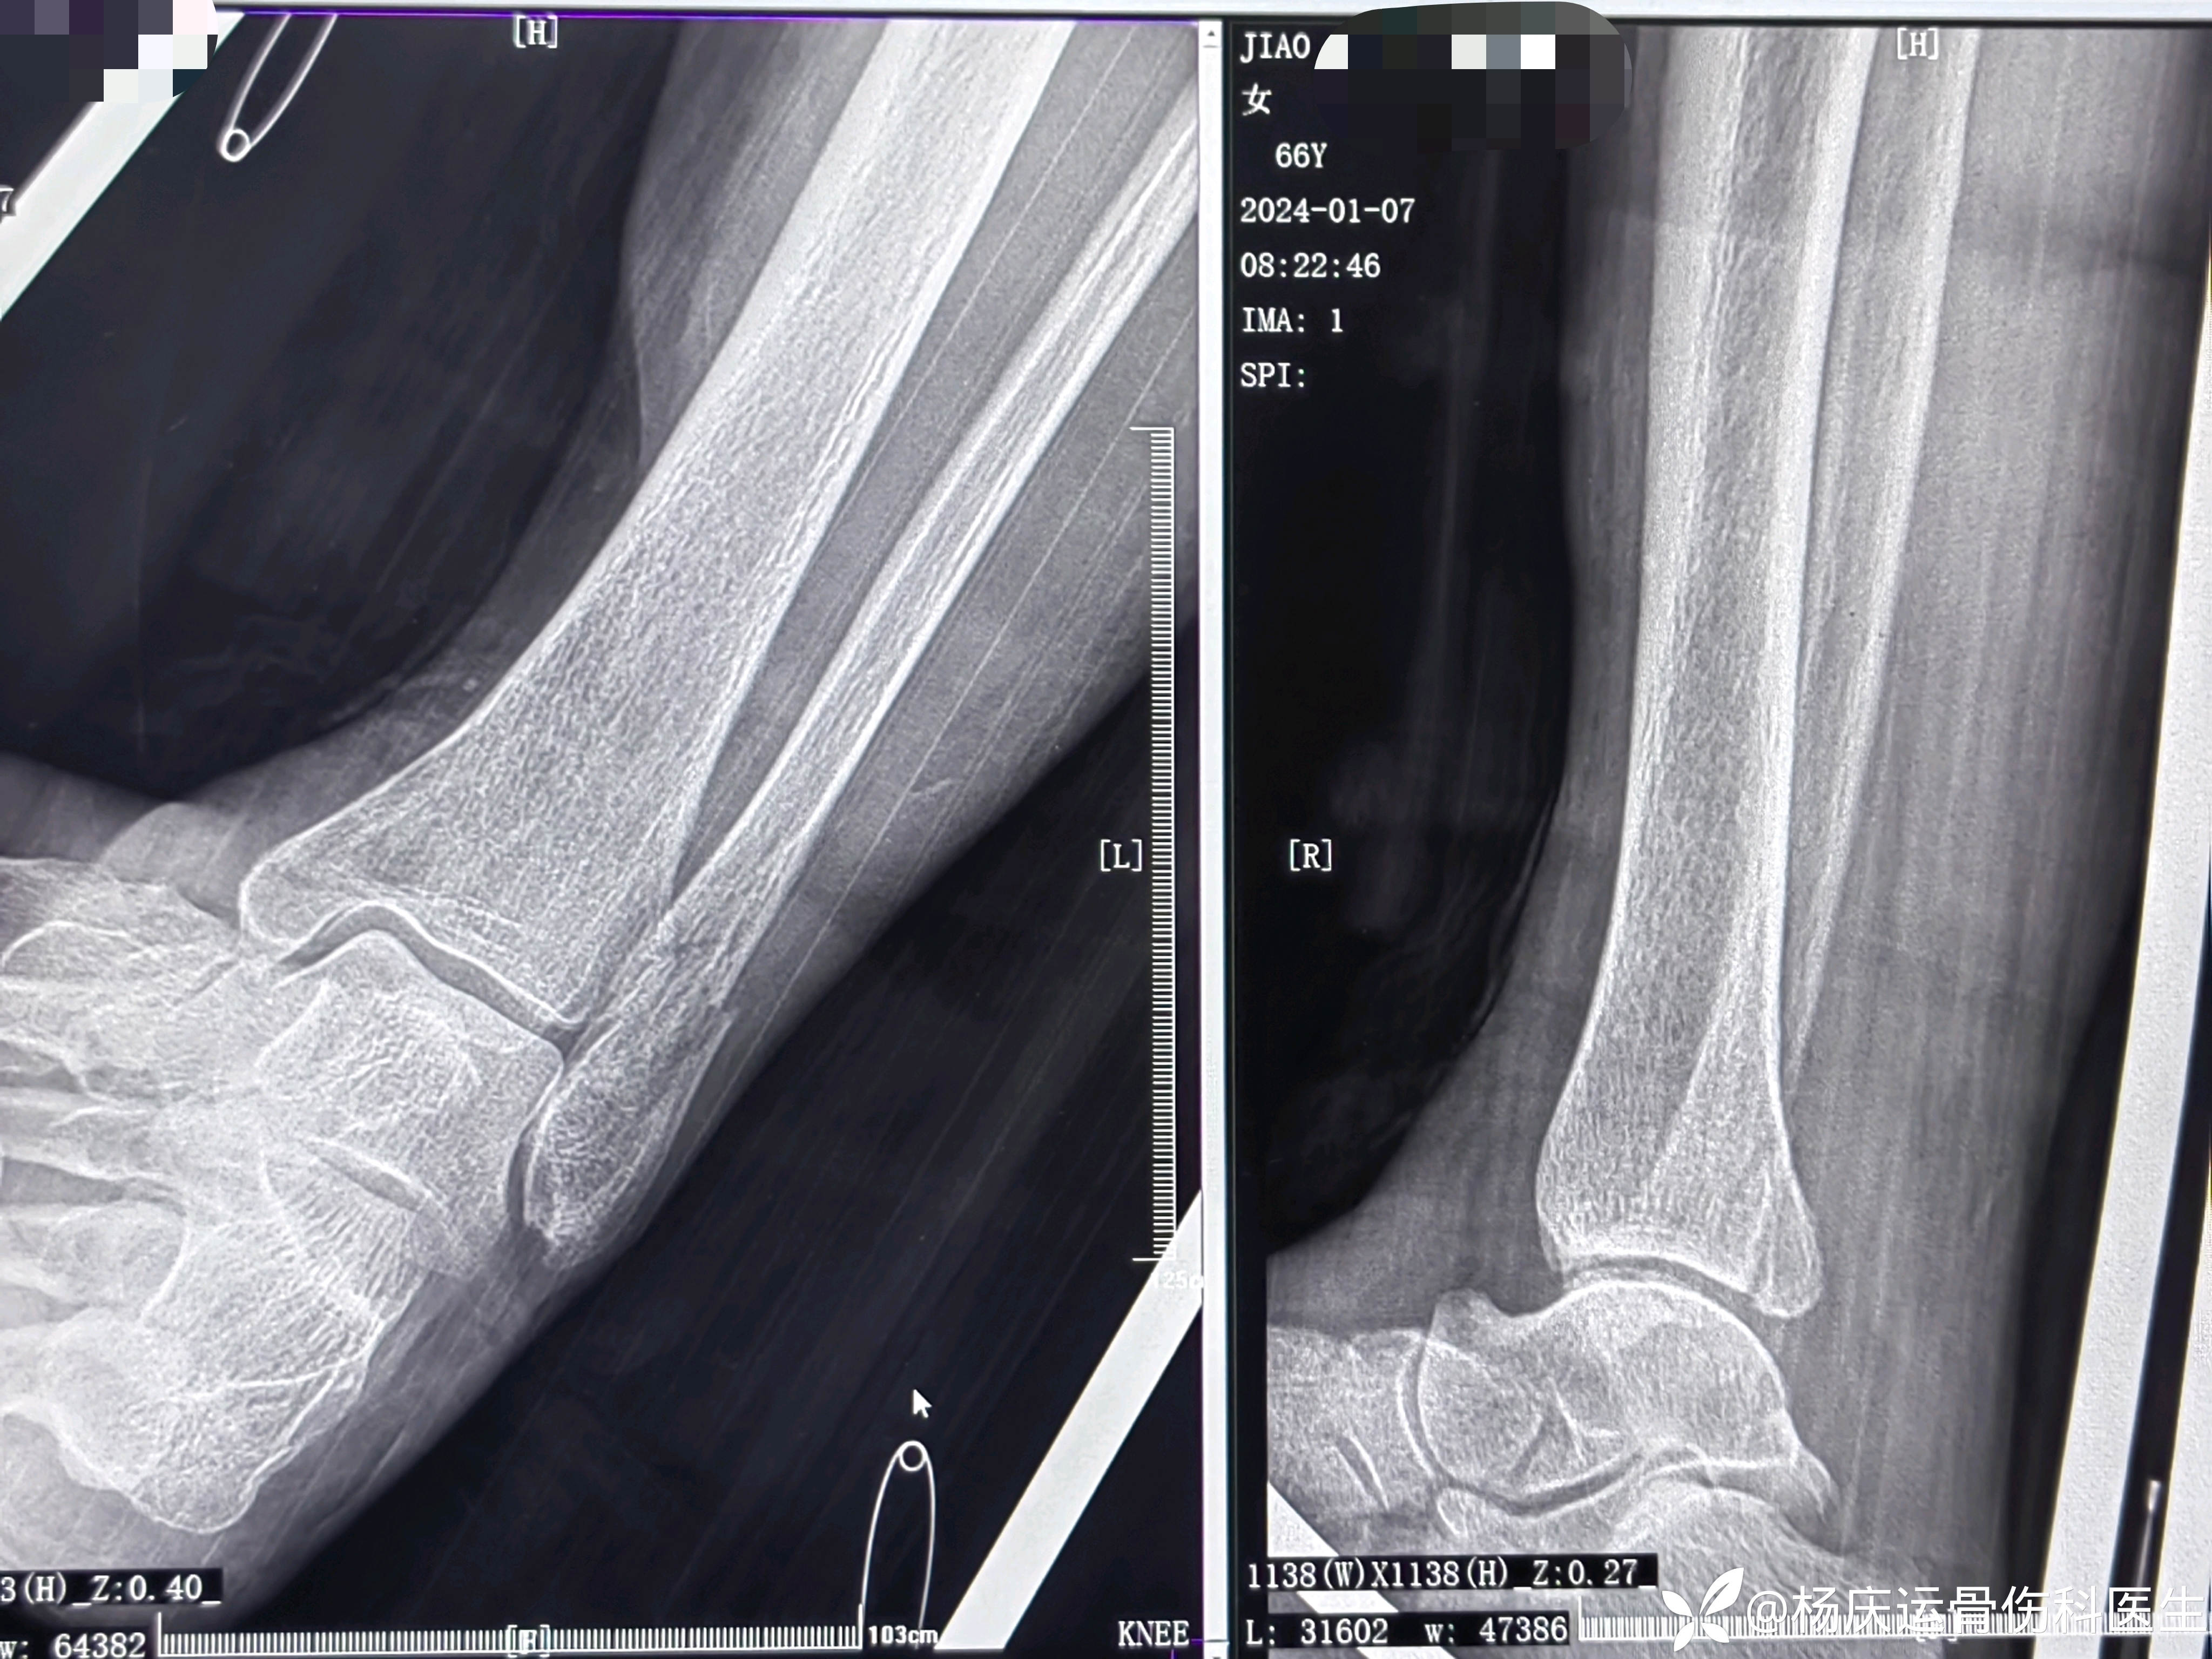

患者矫,女,66岁,左踝扭伤肿痛畸形2小时

初步诊断:左踝关节骨折(L-H分型:旋后外旋型IV)

首诊片